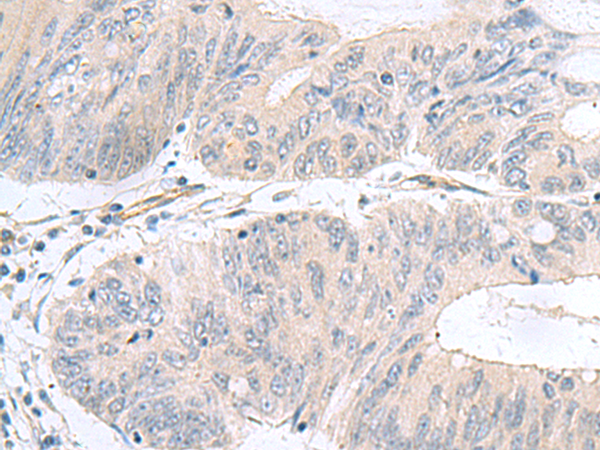

分类: 科研抗体货号: P03298别名: L22mt; RPML25; HSPC158; MRP-L22; MRP-L25应用: WB,IHC反应种属: Human, Mouse, Rat